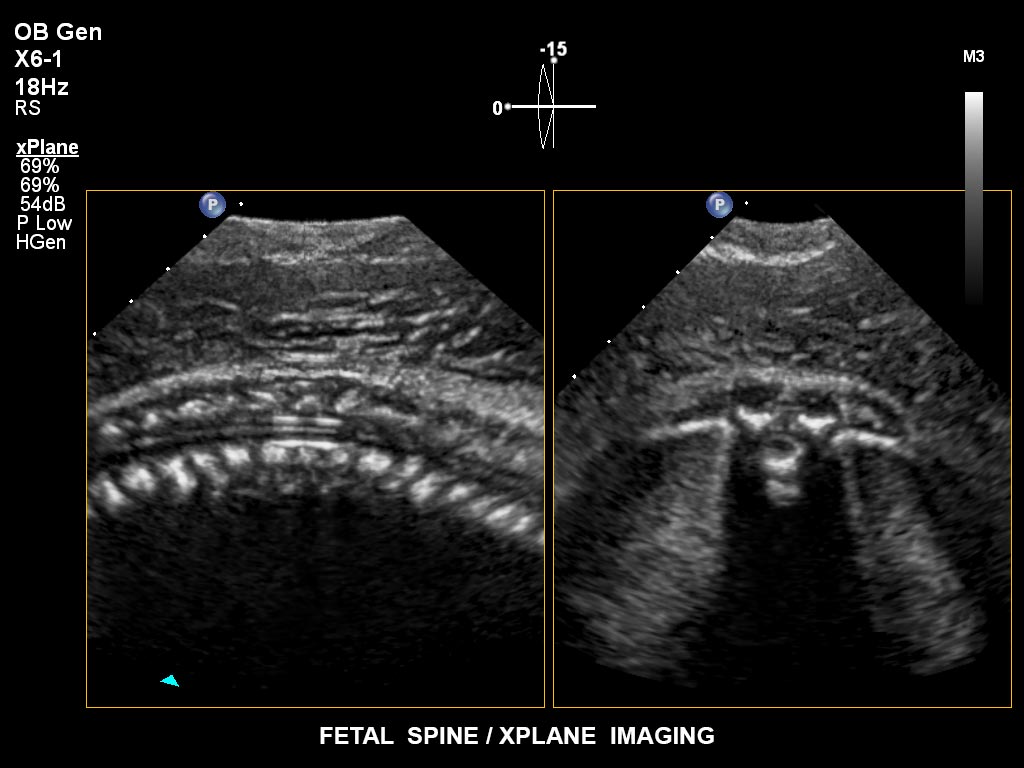

• X6-1 PureWave-xMATRIX Schallkopf für diagnostische Anforderungen, die über die 2D-Bildgebung hinausgehen, setzt mit PureWave neue Massstäbe u.a. bei der Live-Volumenbildgebung und Live-Bildgebung in zwei Ebenen gleichzeitig